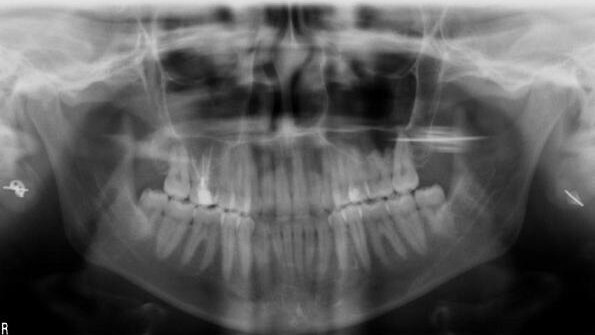

The patient was referred to my office for a complaint regarding the maxillary molar. After examining the patient and looking at her preoperative X-ray, I saw nothing wrong with the existing root-canal treatment, at least concerning the roots, but found a vague image in the sinus that I thought could be related to the maxillary molar and could be the cause of the problem. I asked my assistant to take a panoramic X-ray, which demonstrated a much larger problem inside the sinus but at that point I did not realise the scale of the issue.

A couple of hours later, the patient returned to my office and I took the time to examine the images. In the panoramic view, it was clear that half of the sinus was filled with inflammatory tissue (Fig. 2); in the sectional views, I noticed that the posterior wall of the sinus was non-existent in some places (Figs. 3–5). Potentially, it could be the position of the patient during the root-canal procedure that made NaOCl stagnate on the posterior wall and aggravate the damage.